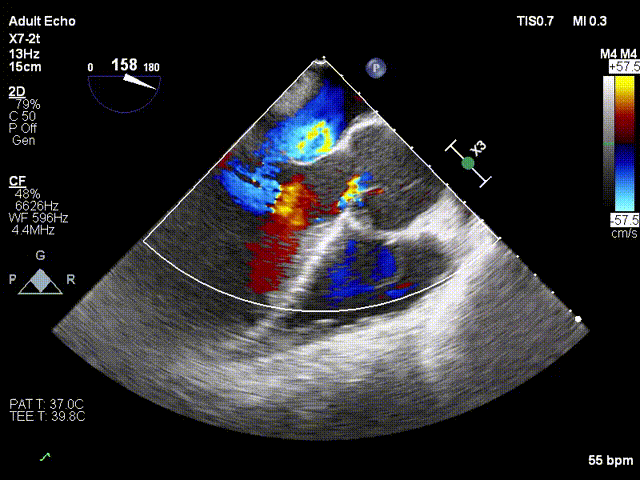

术前超声

术后超声

心脏彩超:提示主动脉瓣大量反流。

检查所见:肺动脉瓣口血流速度57cm/s;主动脉瓣口血流速度240cm/s,平均压差10mmHg,估测主动脉瓣口面积2.06 cm²,有效主动脉瓣口面积指数1.34。二尖瓣口面积5.61cm²,二尖瓣反流分数10%。主动脉瓣反流Vmax 547cm²/s,ERO 0.53cm²;二尖瓣口舒张期血流:E/A=47/61,估测肺动脉平均压5mmHg。

二维超声表现:左房稍大,左室增大,右房室腔内径正常范围,室间隔基底段增厚,左、右室壁厚度正常,运动欠协调,动度尚可。房室间隔连续完整。主动脉瓣增厚毛糙,开放尚可,关闭有间隙,余瓣膜形态、结构、启闭运动尚可。主动脉窦部及升主动脉增宽,肺动脉未见扩张,心包腔未见异常。

彩色多普勒探及主动脉瓣重度反流、二尖瓣轻度反流、三尖瓣微量反流血流。